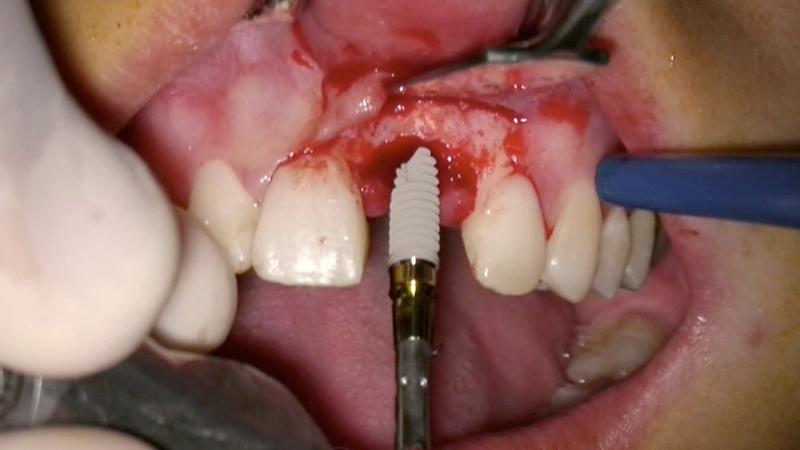

L'obiettivo è inserire un impianto nella cresta ossea rigenerata e ripristinare il volume del tessuto gengivale cheratinizzato nell'area vestibolare circostante.

3. Posizionamento dell'impianto. L'impianto è posizionato centralmente con un'inclinazione palatale per evitare che il foro di accesso della vite interferisse con il bordo incisale del dente provvisorio o con la sua superficie vestibolare (Fig. 13).

Posizionamento dell'impianto

Fig. 13 - Posizionamento dell'impianto.